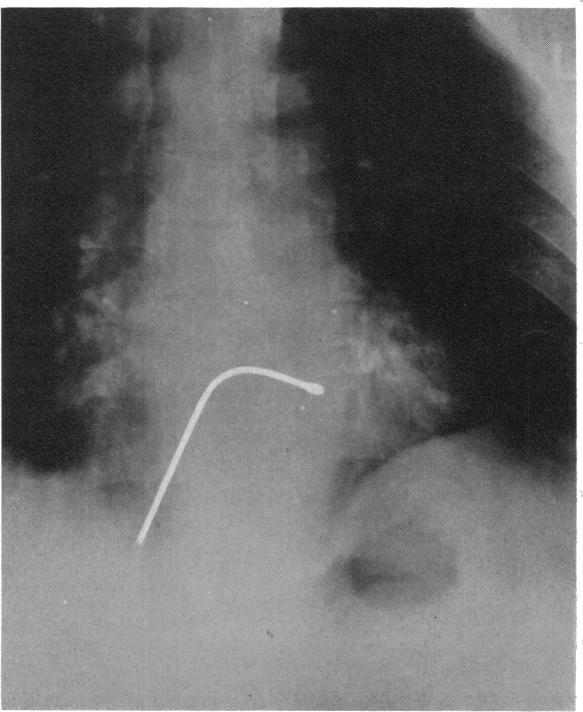

Measurements of sinus impulse conduction from electrogram of bundle of His.

Br Heart J. 1971 Sep;33(5):719-24. doi: 10.1136/hrt.33.5.719.